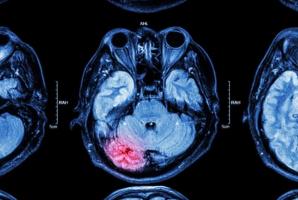

- l'hippocampe, une partie du cerveau est une zone clé dans la formation et l'organisation des souvenirs.